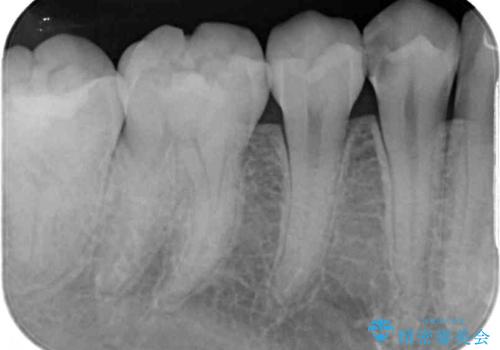

- 奥歯に頻繁に物が挟まるとのことで来院された患者様です。

最近ものが挟まりやすくなったり、冷たいものがしみるようになったりといった症状があり、診査したところ、むし歯や歯質の欠損、不適修復物などが認められました。

処置を行った歯以外にもむし歯と思われる歯が多数ありますが、費用のかかる治療であれば、優先順位をつけて、処置を急ぐ歯から処置を進めて行きました。